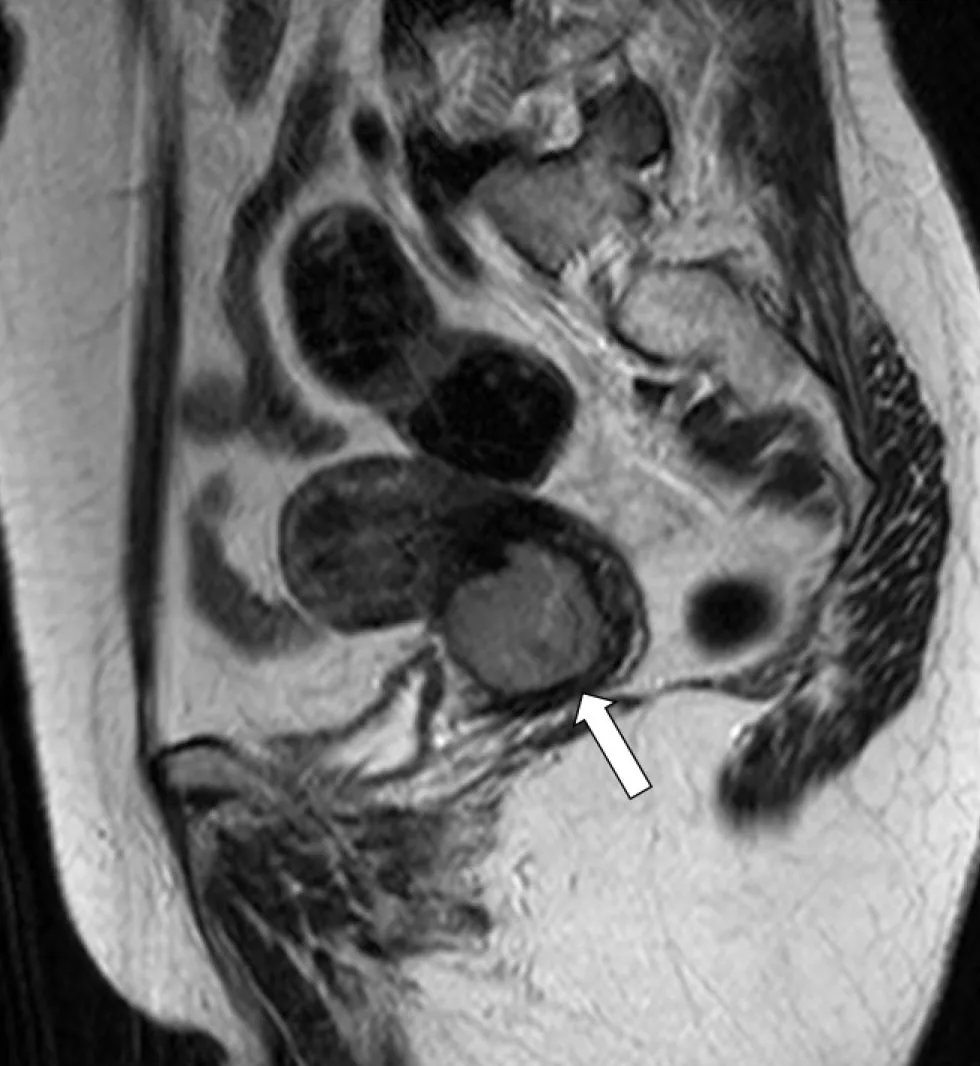

詳解

破題關鍵

這張磁振造影(MRI)T2WI 影像顯示子宮內膜異常增厚且訊號不均勻,結合病患停經後陰道出血的症狀,高度懷疑是子宮內膜癌。

選項拆解

登入查看完整詳解與互動作答